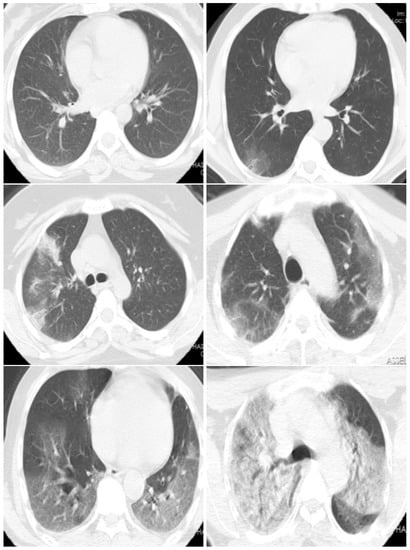

Figure 3. CT scan images examples which have the COVID-19 infection percentages of 0%, 5%, 18%, 40%, 70%, and 80%, respectively. These slices are classified as Normal, Minimal (<10%), Moderate (10–25%), Extent (25–50%), Severe (50–75%), and Critical (>75%), respectively.

In the proposed dataset, we kept the slices that have diagnosis agreement of the two radiologists. In summary, from each CT-scan, we can have between 2 and 45 typical slice images (these slices have close estimation of COVID-19 infection percentage from both radiologists). Figure 2 shows the histogram of number of CT-scans over the number of CT slices. Figure 3 shows examples of slices images with their corresponding COVID-19 infection percentage.